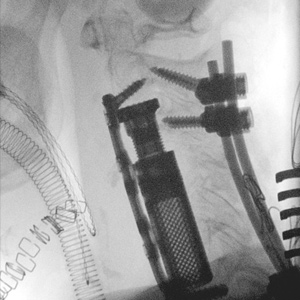

Spinal stenosis (Lumbar) Spinal stenosis (Cervical) Spinal stenosis (Thoracic) Lumbar Disc Herniation Spondylolisthesis Cervical Foraminal Stenosis Vertebroplasty Lumbar Fusion Anterior Cervical Fusion (ACDF) Posterior Cervical Fusion Thoracic Fusion Revision Lumbar Fusion Surgery Facet Joint Cyst Spinal Tumour Minimally Invasive Lumbar Fusion (XLIF) Minimally Invasive Lumbar Fusion (ALIF) Lumbar Fusion (TLIF) Thoraco-lumbar Fusion Lumbar Corpectomy Complex Lumbar Spine Surgery (Spino-pelvic fixation) Complex Cervical Spine Surgery Complex Thoracic Spine Surgery Occipito-cervical Fusion Minimally invasive surgery for thoracic disc herniation Other Related Topics